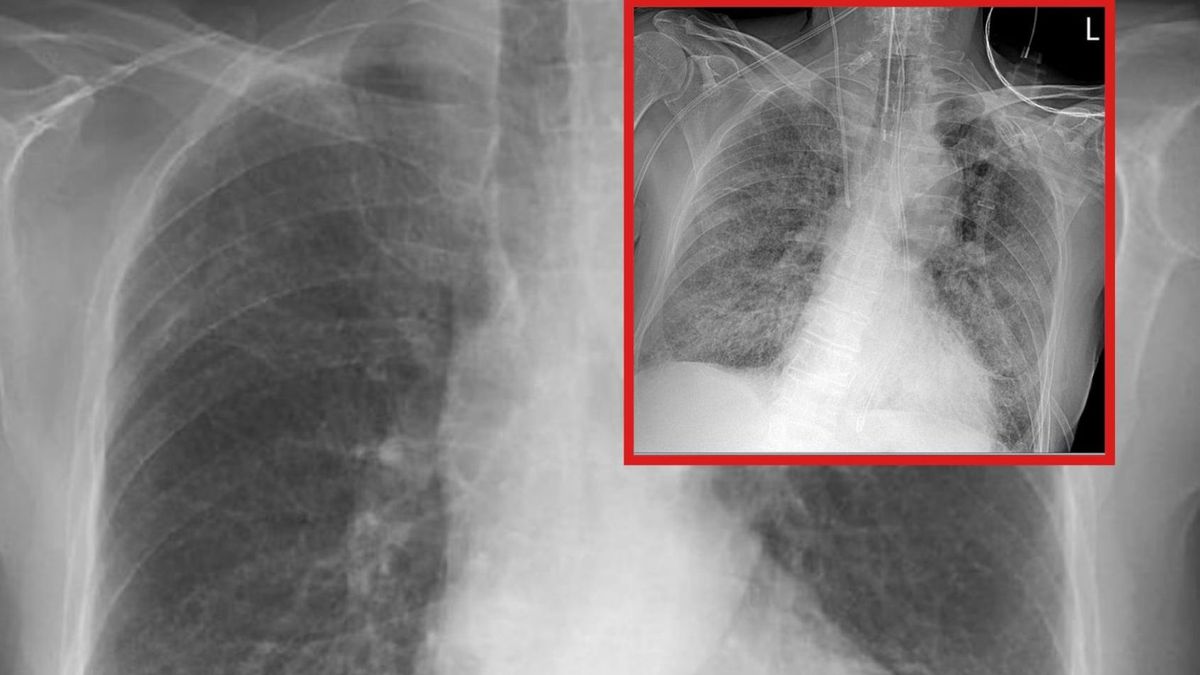

Lekarze od miesięcy przekonują, że koronawirus powoduje w płucach chorego ogromne spustoszenia. By uciąć spekulacje, publikują na to dowody - zdjęcia RTG, na których widać zmiany wywołane przez SARS-CoV-2. Tak też zrobił Tomasz Rezygent, lekarz w trakcie specjalizacji z chorób wewnętrznych, publikując w sieci 2 fotografie, na których widać stan płuc pacjenta z COVID-19.

Rezydent opublikował dwie fotografie RTG, które były wykonane u jednego chorego z pozytywnym wynikiem na koronawirusa. "Pierwsze RTG wykonano przy przyjęciu do szpitala, u pacjenta dodatniego z osłabieniem i gorączką, jeszcze bez duszności. Drugie wykonano u tego samego chorego po 7 dniach hospitalizacji, już w skrajnej niewydolności oddechowej wymagającej respiratoroterapii" - opisuje lekarz.

Obraz płuc, w którym 80 proc. powierzchni narządu jest zajęte przez wirusa

Obraz płuc, w którym 80 proc. powierzchni narządu jest zajęte przez wirusa © Tomasz-Rezydent

Wyjaśnia, że ciemnie obszary płuca na pierwszym zdjęciu są w większości z niezmienionej jeszcze chorobowo tkanki, natomiast nakrapiane mlecznie płuca są praktycznie w całości zajęte (odpowiadają 80 proc. zajętego miąższu w tomografii komputerowej).

"Jeden pacjent, siedem dni różnicy. Jeden wredny wirus. Czy miał choroby współistniejące? Tak. Czy to one go zabiły? Nie. Tylko covid" - podsumowuje rezydent.